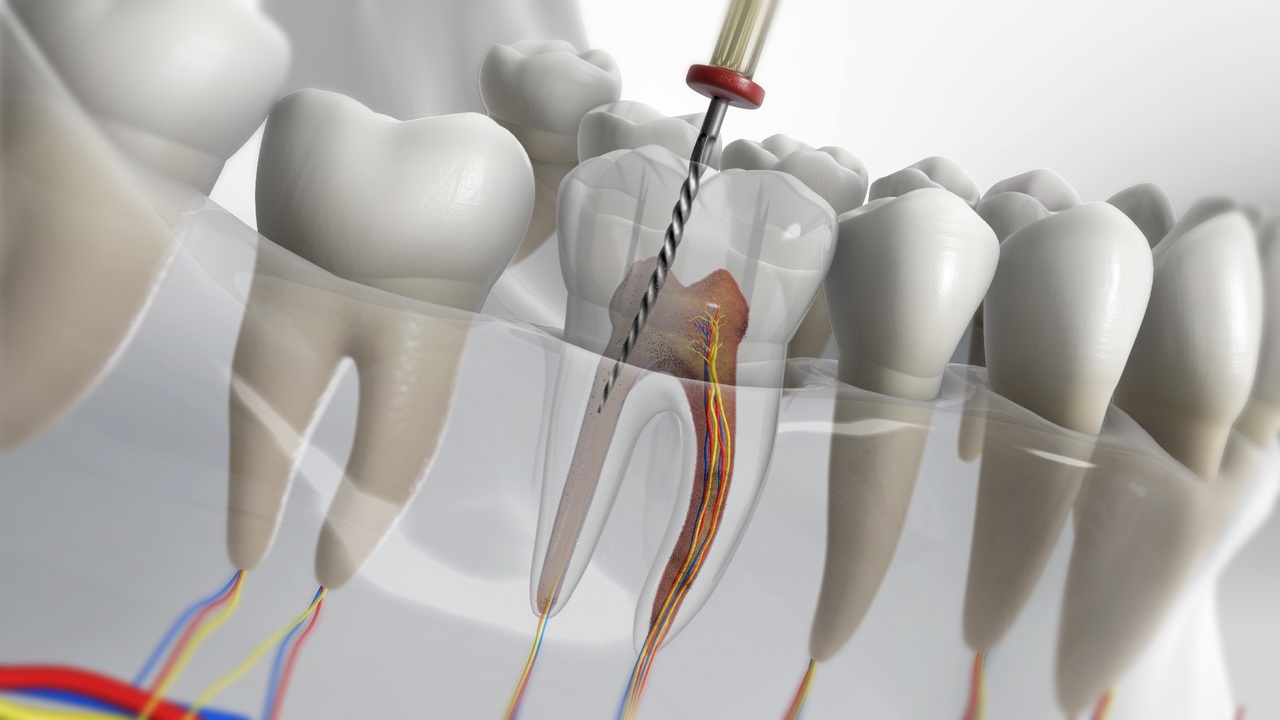

TRATAMIENTO DE CONDUCTO O ENDODONCIA

Consiste en remover el nervio y desinfectar el conducto radicular para luego ensancharlo y lograr el suficiente espacio para colocar un material de relleno dentro de la raíz y evitar un abceso.